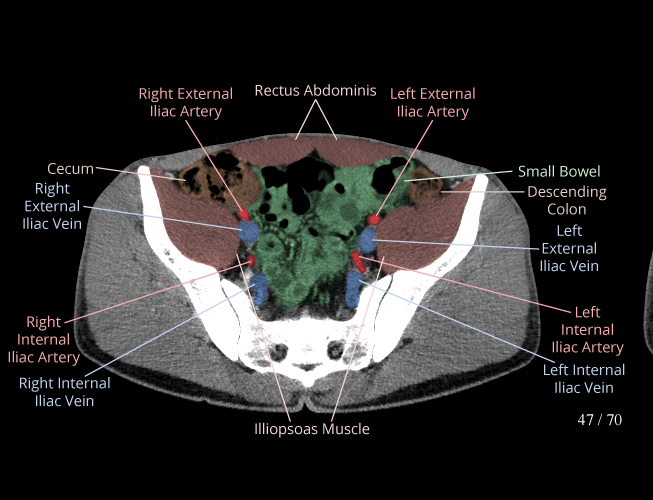

Pelvis

Covers pelvic MRI anatomy.